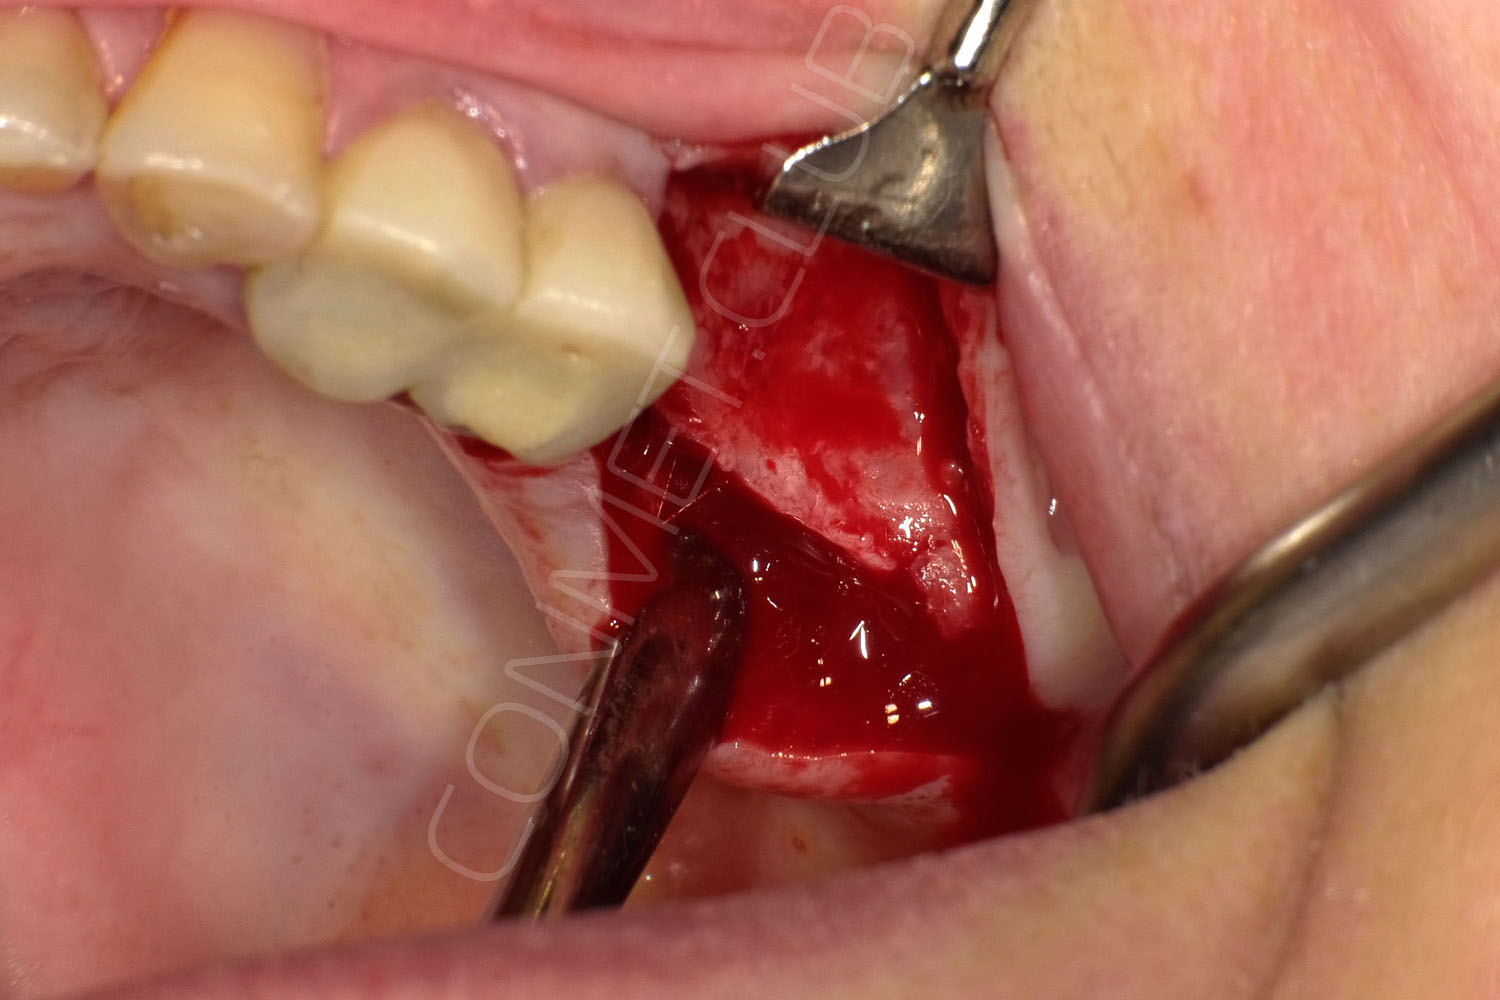

Сама же операция длиться 20-50 минут в зависимости от количества утраченных зубов. В процессе этой операции, после проведенной местной анестезии, делается разрез на слизистой, она приподнимается и субпериостальный имплантат укладывается на кость. После этого рана фиксируется несколькими швами и все! Через 10-14 дней мягкие ткани срастаются и надкостница надежно удерживает имплантат на месте. Нет необходимости ждать несколько месяцев, как это бывает в случае с внутрикостными винтовыми имплантатами.

И в-четвертых: небольшой фрагмент из операции по восстановлению всех утраченных зубов на верхней челюсти. По сути эта операция полностью повторяет протокол и этапность операции представленной в первой части статьи, за исключением того, что искусственные зубы были зафиксированы сразу после операции. Со слов самой пациентки, процесс жевания был совершенно безболезненным с самого первого дня.